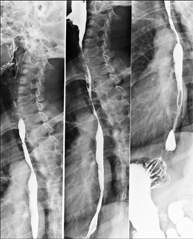

Tècnica que usa els raigs X a través de la qual s'obtenen imatges de la columna dorsal per al seu estudi. Indicacions: traumatisme, dolor, escoliosi. - Esofagograma

Prova diagnòstica que consisteix en obtenir imatges radiològiques en moviment de l'esòfag mitjançant l'ús de raigs X (fluorosòpia) i d'un contrast opac baritat que s'administra per via oral.

Tècnica que usa els raigs X a través de la qual s'obtenen imatges de la columna cervical per al seu estudi. Indicacions: traumatisme, dolor cervical. - RX Columna dorsal

Tècnica que usa els raigs X a través de la qual s'obtenen imatges de la columna dorsal per al seu estudi. Indicacions: traumatisme, mal d'esquena. - RX Columna lumbar

Tècnica que usa els raigs X a través de la qual s'obtenen imatges del sacre i del còccix per al seu estudi. Indicacions: traumatisme, dolor sacre o coccigi. - Telerradiologia columna

Tècnica que usa els raigs X a través de la qual s'obtenen imatges de tota la columna vertebral per al seu estudi, amb la valoració especialment de la presència d'escoliosi i dismetries pèlviques.

Tècnica que usa els raigs X a través de la qual s'obtenen imatges de tota la columna vertebral per al seu estudi, amb la valoració especialment de la presència d'escoliosi i dismetries pèlviques. - Telematria EEII (Extremitats Inferiors)